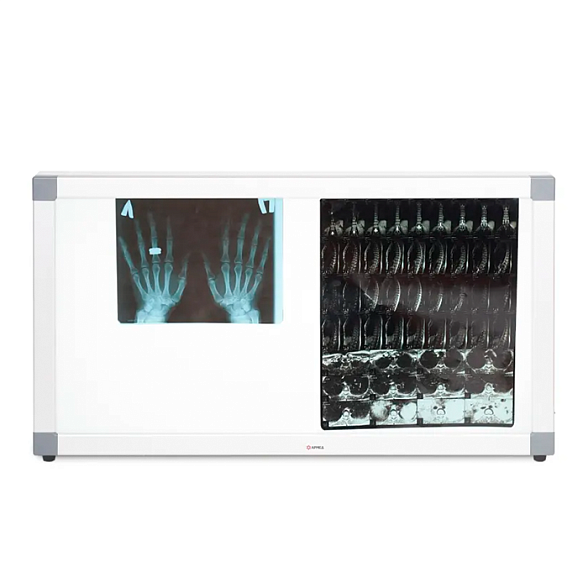

Daray DX4101LED Single Panel X-Ray Film Viewer - негатоскоп

Негатоскоп Daray DX4101LED: Профессиональная оценка рентгеновских снимков

Негатоскоп Daray DX4101LED — это современный и надежный просмотровый стол, предназначенный для точной и комфортной интерпретации рентгеновских, МРТ, КТ и других медицинских снимков. Он заменяет устаревшие люминесцентные модели, предлагая врачам-рентгенологам, травматологам, стоматологам и ветеринарам совершенный инструмент для ежедневной диагностической работы.

Однородная яркая LED-подсветка без мерцания и горячих точек обеспечивает идеальные условия для чтения даже самых плотных участков снимка, снижая нагрузку на зрение и минимизируя риск диагностических ошибок.

- Равномерное освещение: Специальная рассеивающая панель создает однородный световой поток по всей площади экрана без темных углов или пересветов, что критически важно для корректной оценки плотности тканей.

Области применения

Daray DX4101LED незаменим везде, где требуется детальный анализ медицинских изображений на пленке: в государственных и частных поликлиниках, больницах, травмпунктах, стоматологических центрах, ветеринарных клиниках, а также в научно-исследовательских учреждениях.

| Размер полезной области просмотра | 430 x 350 мм (подходит для стандартных снимков 35х43 см) |

Подойдет ли он для просмотра крупноформатных снимков, например, 35х43 см?

Да, полезная площадь экрана (430х350 мм) как раз рассчитана на стандартные снимки размером 35х43 см (14" x 17").